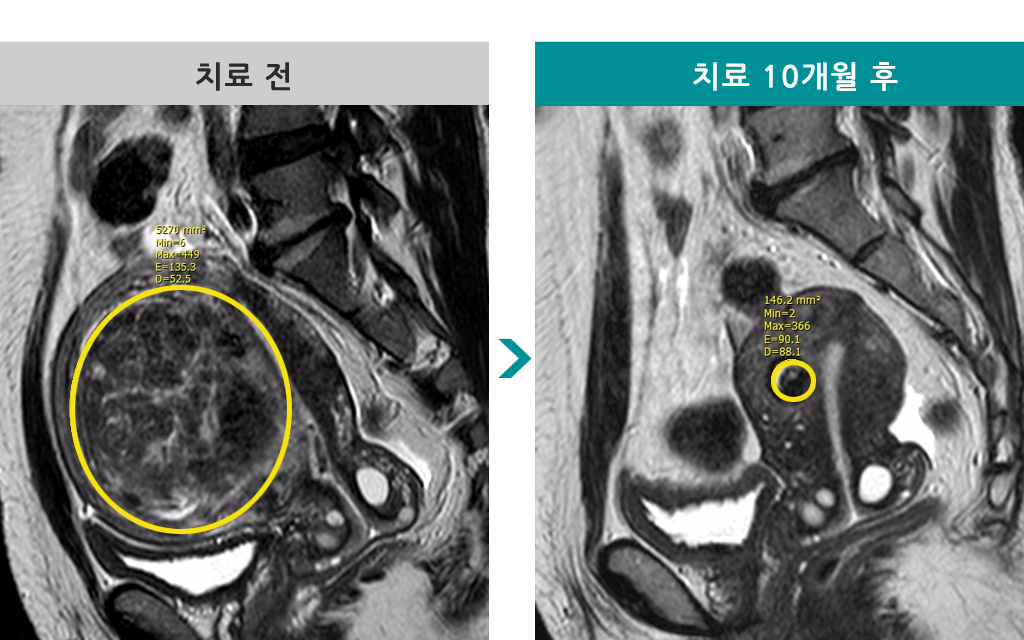

41세 [자궁선근증 색전술] 전후 MRI사진 비교